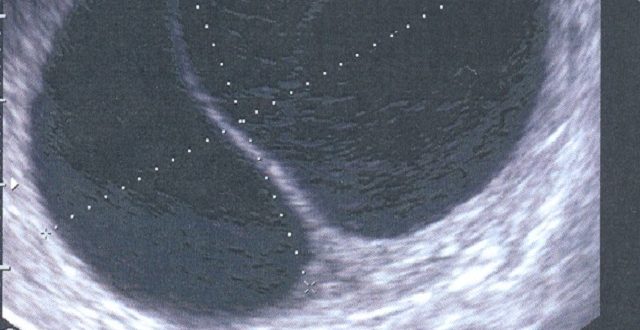

УЗИ: есть жидкость, но нет желтого тела

Желтое тело на УЗИ – хорошо или плохо Некоторые пациентки переживают, когда у них во время УЗИ малого таза в яичнике находят желтое тело. Такие опасения беспочвенны –…